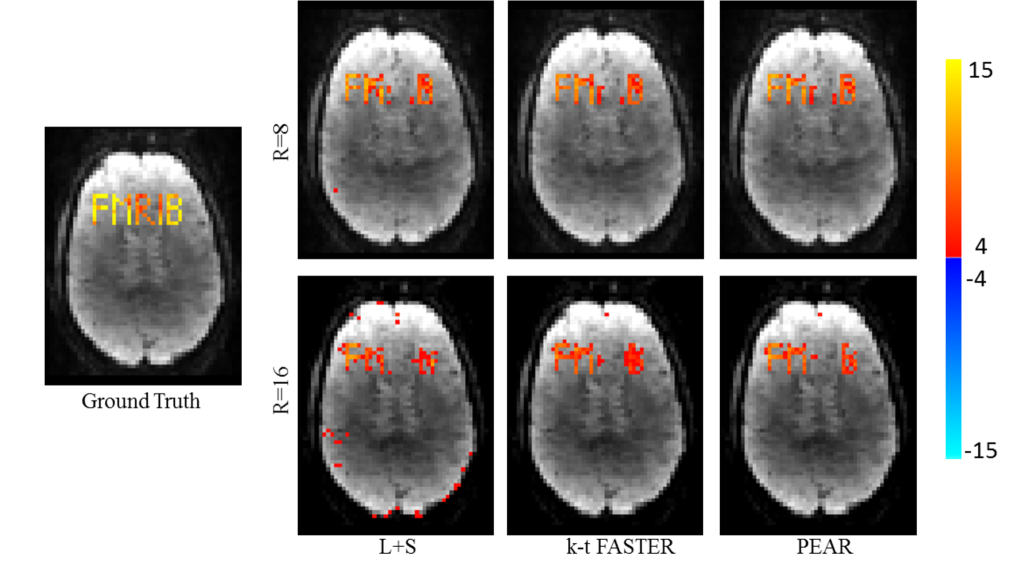

III.1 Experiment 1: Purely synthetic simulation

In this experiment, we simulated a phantom consisting of 5 Regions of Interest (ROIs). Each ROI is spatially formed as a single letter from the letters “FMRIB”, and contains one of 5 purely synthetic timecourses, generated as follows. The letters “F” and “I” were purely periodic timecourses where “F” contains a single frequency and “I” contains a mixture of three frequencies, “R” was a purely aperdioc timecourse, and “M” and “B” were a superposition of periodic and aperiodic timecourses. The phantom was added to a realistic background fMRI dataset, to form a 2D fMRI sequence with known functional timecourses, of size , with time points. The timecourses and their spatial locations in the simulated image are shown in Fig. 2 (left and top).

Undersampling was carried out in the k-t space. We examined two undersampling ratios, first by taking 8 radial projections at each timepoint (corresponding to acceleration ratio of R=8 relative to a fully-sampled, maximally efficient Cartesian acquisition). We then repeated the experiment using only 4 radial projections at each timepoint (corresponding to R=16). This simulates one slice of a hybrid radial-Cartesian trajectory, which rotates an EPI trajectory within 3D k-space Chiew et al. [2016]. An additive white Gaussian noise with zero mean was added to the samples in the k-space domain to obtain SNR of dB. For PEAR, was examined in the range of 0.45-3.4 and was selected as experimentally. For L+S, was examined in the range of 1.1-3.4 and was examined in the range of 0.45-3.4. These parameters were selected as and experimentally (the values for are provided after normalization with respect to the standard deviation of the data).

To examine the correspondence of the reconstruction with the ground-truth, we performed regression against the original timecourses using General Linear Model (GLM)Jenkinson et al. [2012]. Figure 3 shows the F-test results as null-corrected z-statistics mapsBeckmann et al. [2005], for the ground-truth data (fully sampled image without the addition of noise), L+S, k-t FASTER and PEAR, for both R=8 and R=16. All maps are thresholded at and shown with color scale mapped between .

It can be seen that PEAR provides the most reliable result, being the only method that almost perfectly recovers both “M” and “B” with minimum false positive errors at R=16. In addition, we see that L+S is unable to recover the aperiodic timecourse “R”, as opposed to both k-t FASTER and PEAR thanks to their fixed-rank component.

An interesting analysis is the contribution of each component in PEAR. Figure 4 shows the GLM results for the A and P components of PEAR separately (for R=16), where the z-statistics maps are thresholded at and shown with color scale mapped between . Note that the sum of the null-corrected z-statistics maps of A and P is not equal to the z-statistics map of PEAR, due to the null-correction applied for each map, that depends with each map’s noise level. However, the separation of PEAR into periodic and fixed rank components is clearly demonstrated. The A component highly corresponds with the letter “R” which is a purely aperiodic timecourse, and with the letters “M” and “B” that include an aperiodic part. The P component highly corresponds to the letters “F” and “I” which are purely periodic timecourses, and to the letters “M” and “B” that include an periodic part. As demonstrated, this separation allows better modelling and leads to better recovery compared to k-t FASTER and L+S. Another analysis is presented in Fig. 5, where example portions of the mean timecourses from the five letter ROIs are shown for the ground truth, L+S, k-t FASTER and PEAR reconstruction results, including the timecourses for the A and P components of PEAR separately. The timecourses are shown in arbitrary units, to allow proper examination of their structure. It can be seen that as expected, L+S is limited in its ability to track the rapid changes that appear in the letter “R”. In addition, the P component of PEAR indeed contains the periodic part of the signal, and therefore exhibits high correspondence with letters that are fully periodic (“F” and “I”).